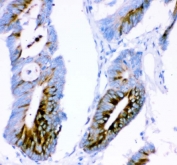

IHC staining of FFPE human colon cancer tissue with ATXN1 antibody. HIER: boil tissue sections in pH8 EDTA for 20 min and allow to cool before testing.